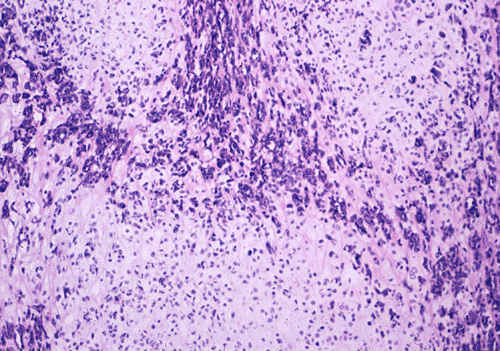

The basophilic background is composed of tightly packed, undifferentiated spindle cells without significant deposition of collagen fibers in between (Panel E). Panels  F, G, and H are taken from a different area of the tumor and were not posted on the question web-page. The pathologic change in these areas are very common among mesenchymal chondrosarcoma and should be looked. These include lobules of highly cellular tumor separated by fibrous connective tissue septa (Panel F) and Prominent tumor vascularity with highly branching vessels which (with a bit of imagination!) resemble deer "antlers" or "staghorns"(Panel G and H). This pattern of vessel distribution is similar to that seen in hemangiopericytoma (an uncommon soft tissue tumor) and is therefore often described as a “hemangiopericytoma-like” vascular pattern. The overall gross and light microscopic features in this case are consistent with a diagnosis of primary extraskeletal mesenchymal chondrosarcoma.

Grossly, mesenchymal chondrosarcoma typically appears as a circumscribed, lobulated, solid mass with a soft, fleshy, grey-white to gray-pink cut surface. Scattered deposits of cartilage and/or bone of varying size may be grossly recognized, and areas of hemorrhage and necrosis may be present. Tumor size is variable with reported tumor diameters ranging from 3 - 37 cm. Microscopically, mesenchymal chondrosarcomas are biphasic tumors composed of sheets of round to spindle-shaped primitive mesenchymal cells surrounding discrete islands of hyaline cartilage. The proportions of primitive and cartilaginous elements vary widely among tumors and even within different areas of the same tumor. Cartilaginous differentiation ranges in degree and extent from small foci with high-grade nuclear features to large areas of well-differentiated cartilage. The primitive mesenchymal component is highly vascular, typically containing large numbers of highly branched vascular channels (the so-called “hemangiopericytoma-like pattern”).